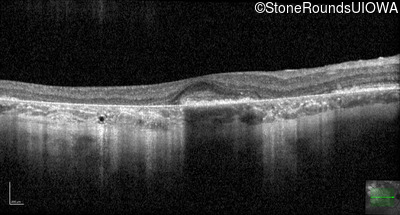

Age at visit: 30 years

This 30 year old man first noticed poor vision in dim light when he was five years old. His visual acuity began to fall in his early 20's.

Age at visit: 32 years

Age at visit: 34 years

Age at visit: 35 years

Age at visit: 37 years

Age at visit: 39 years

Age at visit: 40 years

Age at visit: 42 years